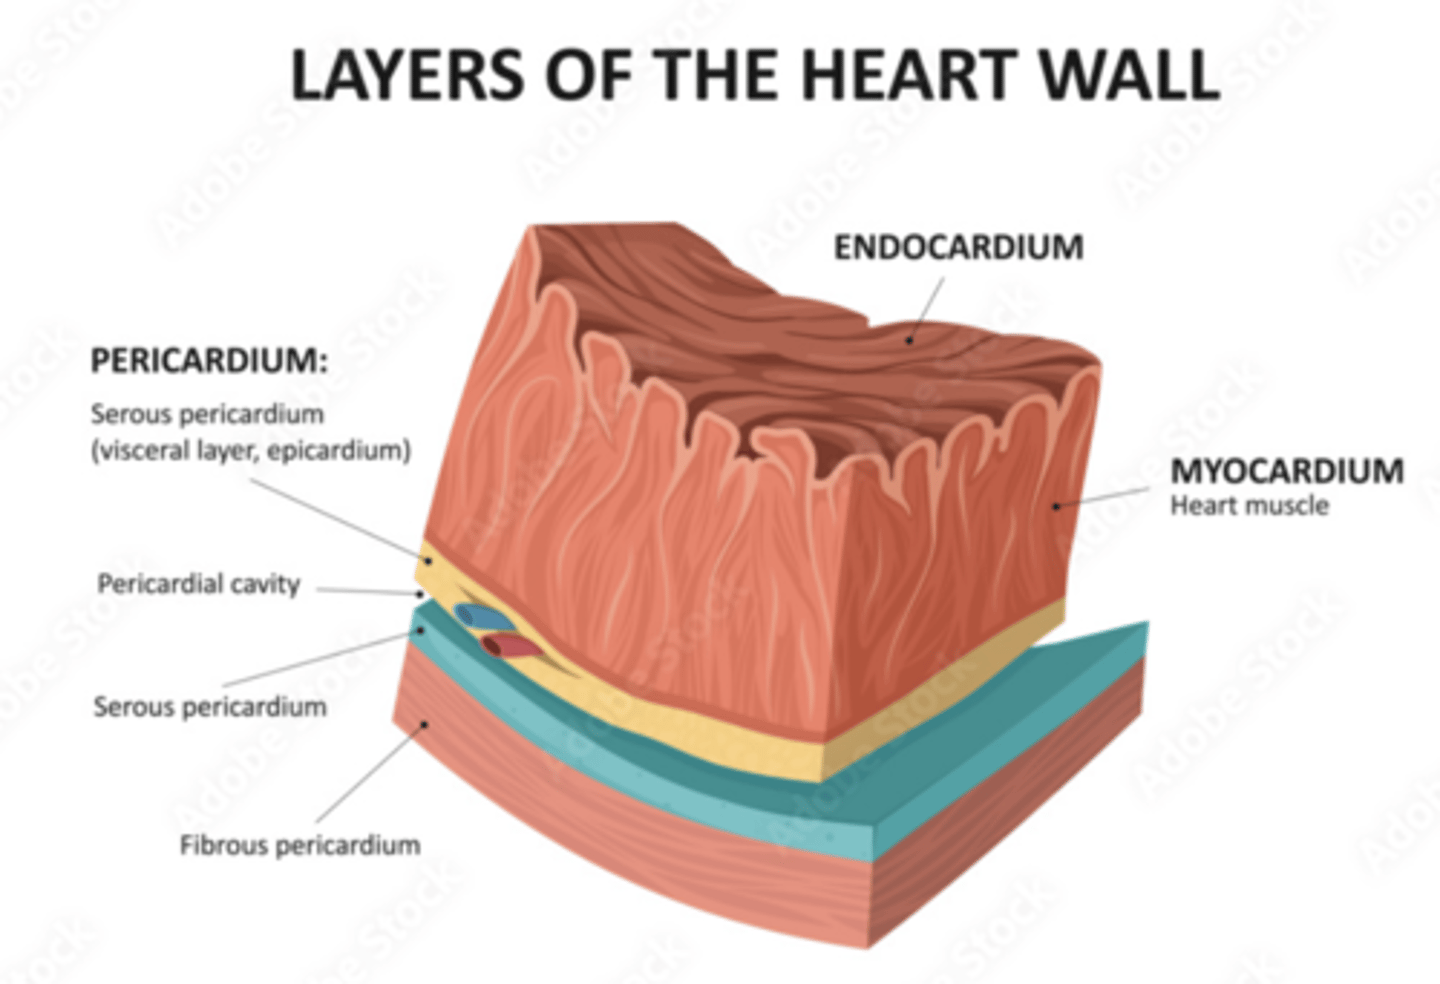

What are the layers of the pericardium?

The pericardium consists of two main layers:

- the fibrous pericardium

- the serous pericardium

How is divided the serous pericardium?

. Visceral layer or Epicardium (innermost). Adheres to the heart

. Parietal layer (outermost)

Between these layers is the pericardial fluid (pericardium cavity )

What is the fibrous pericardium?

the tough, outer layer

protects the heart

maintains its position in the thorax.

defines the boundaries of the medium mediastinum

What are the layers of the heart?

Epicardium: outermost covering.

Myocardium (right << left)

Endocardium or endothelium: inner thin layer of simple squamous epithelium